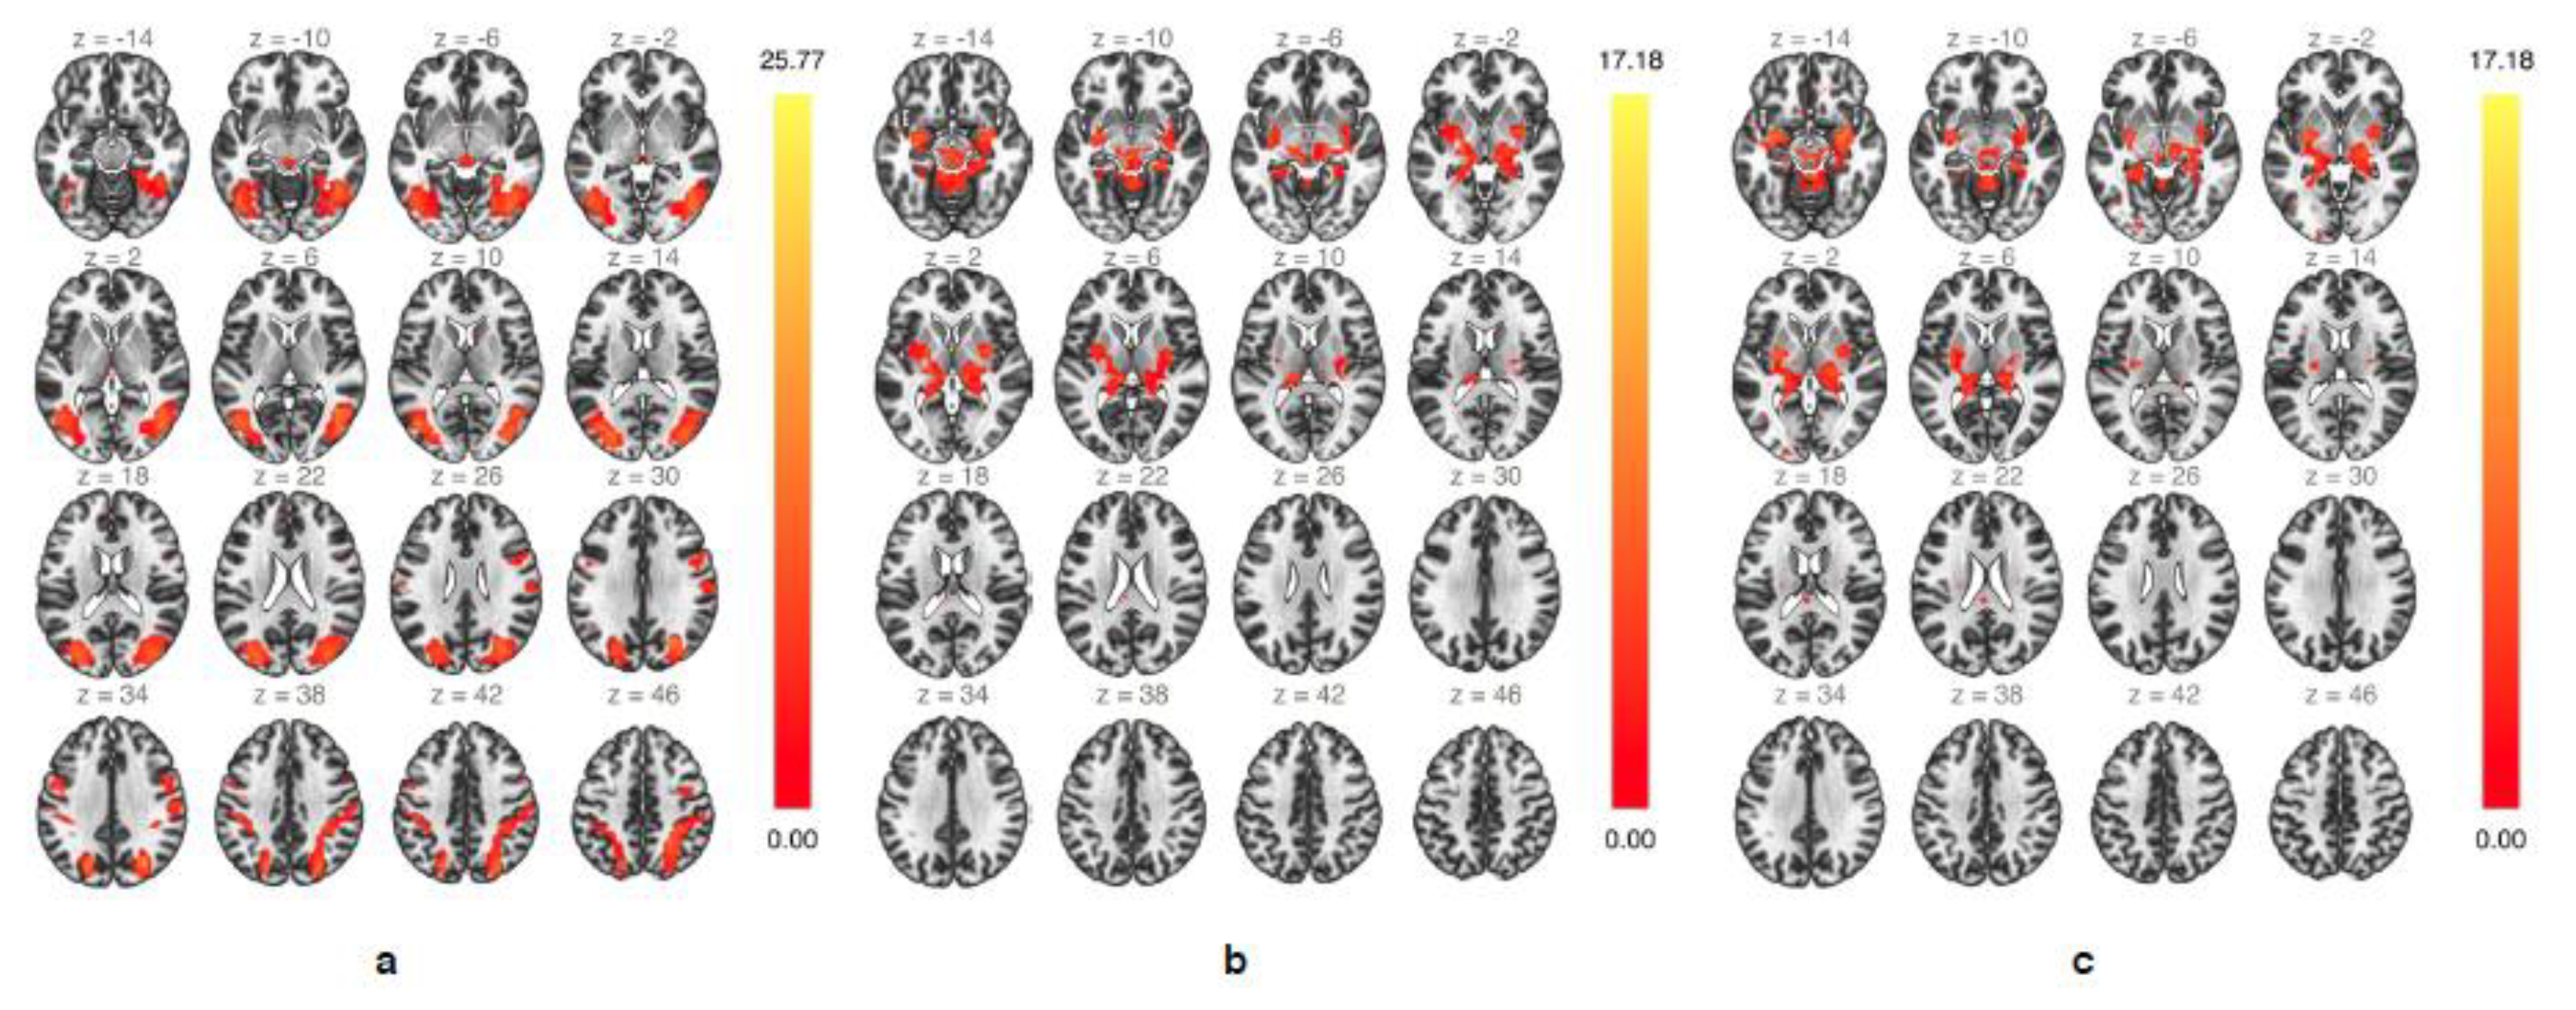

3.3. Functional Connectivity—ICA

3.4. Functional Connectivity—Seed-To-Voxel